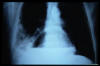

Fibrosis pulmonar. ICC.